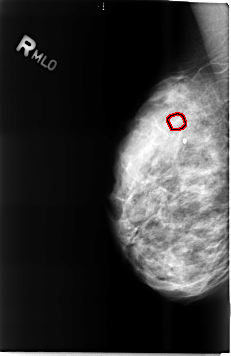

B_3485_1.RIGHT_MLO

RIGHT_MLO LINES 4616 PIXELS_PER_LINE 2992 BITS_PER_PIXEL 12 RESOLUTION 50 OVERLAY

FILE: B_3485_1.RIGHT_MLO.OVERLAY

TOTAL_ABNORMALITIES 1

ABNORMALITY 1

LESION_TYPE CALCIFICATION TYPE PUNCTATE DISTRIBUTION CLUSTERED

ASSESSMENT 4

SUBTLETY 3

PATHOLOGY BENIGN

TOTAL_OUTLINES 1

BOUNDARY